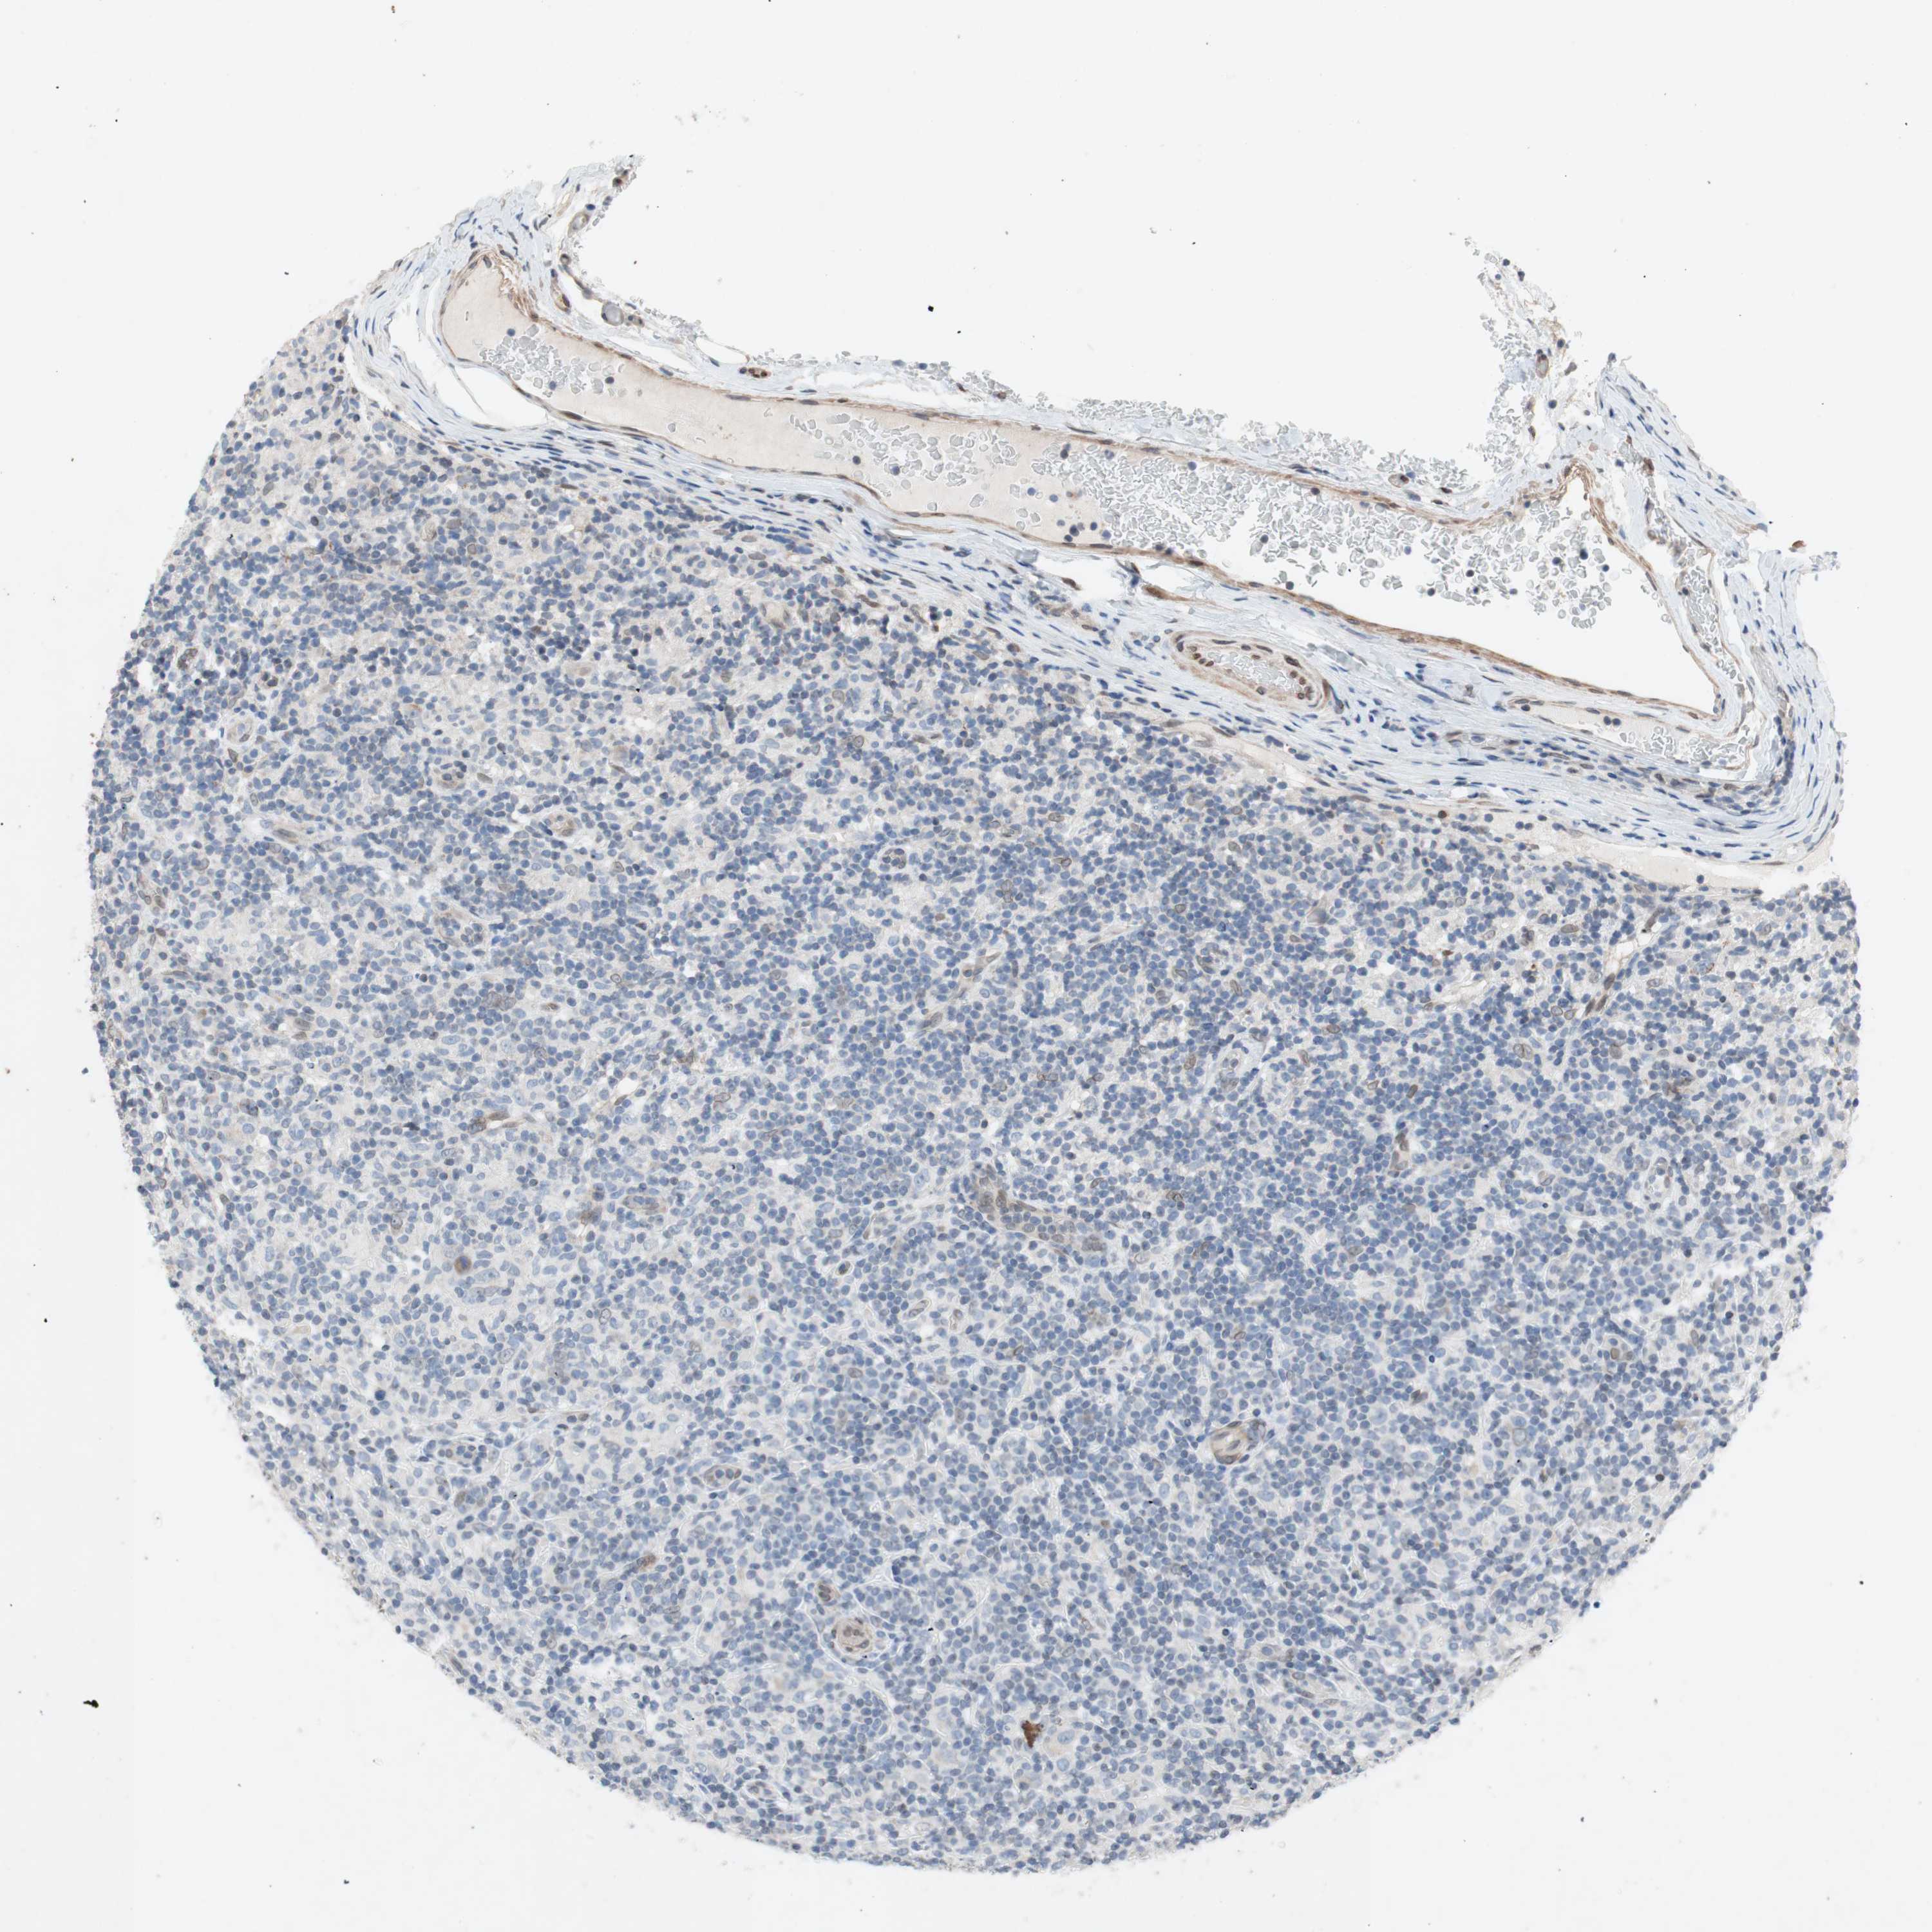

CANCER LYMPHOMA Show tissue menu

LYMPHOMA - Protein expressioni

A mouse-over function shows sample information and annotation data. Click on an image to view it in a full screen mode. Samples can be filtered based on level of antibody staining by selecting one or several of the following categories: high, medium, low and not detected. The assay and annotation is described here.

Antibody staining in the annotated cell types in the current human tissue is reported as not detected, low, medium, or high, based on conventional immunohistochemistry profiling in selected tissues. This score is based on the combination of the staining intensity and fraction of stained cells.

Each image is clickable and will lead to virtual microscopy that enables deeper exploration of all samples and also displays staining intensity scores, fraction scores and subcellular localization as well as patient and tissue information for each sample.

Malignant lymphoma, non-Hodgkin's type, High grade

Hodgkin's disease, NOS

Malignant lymphoma, non-Hodgkin's type, Low grade